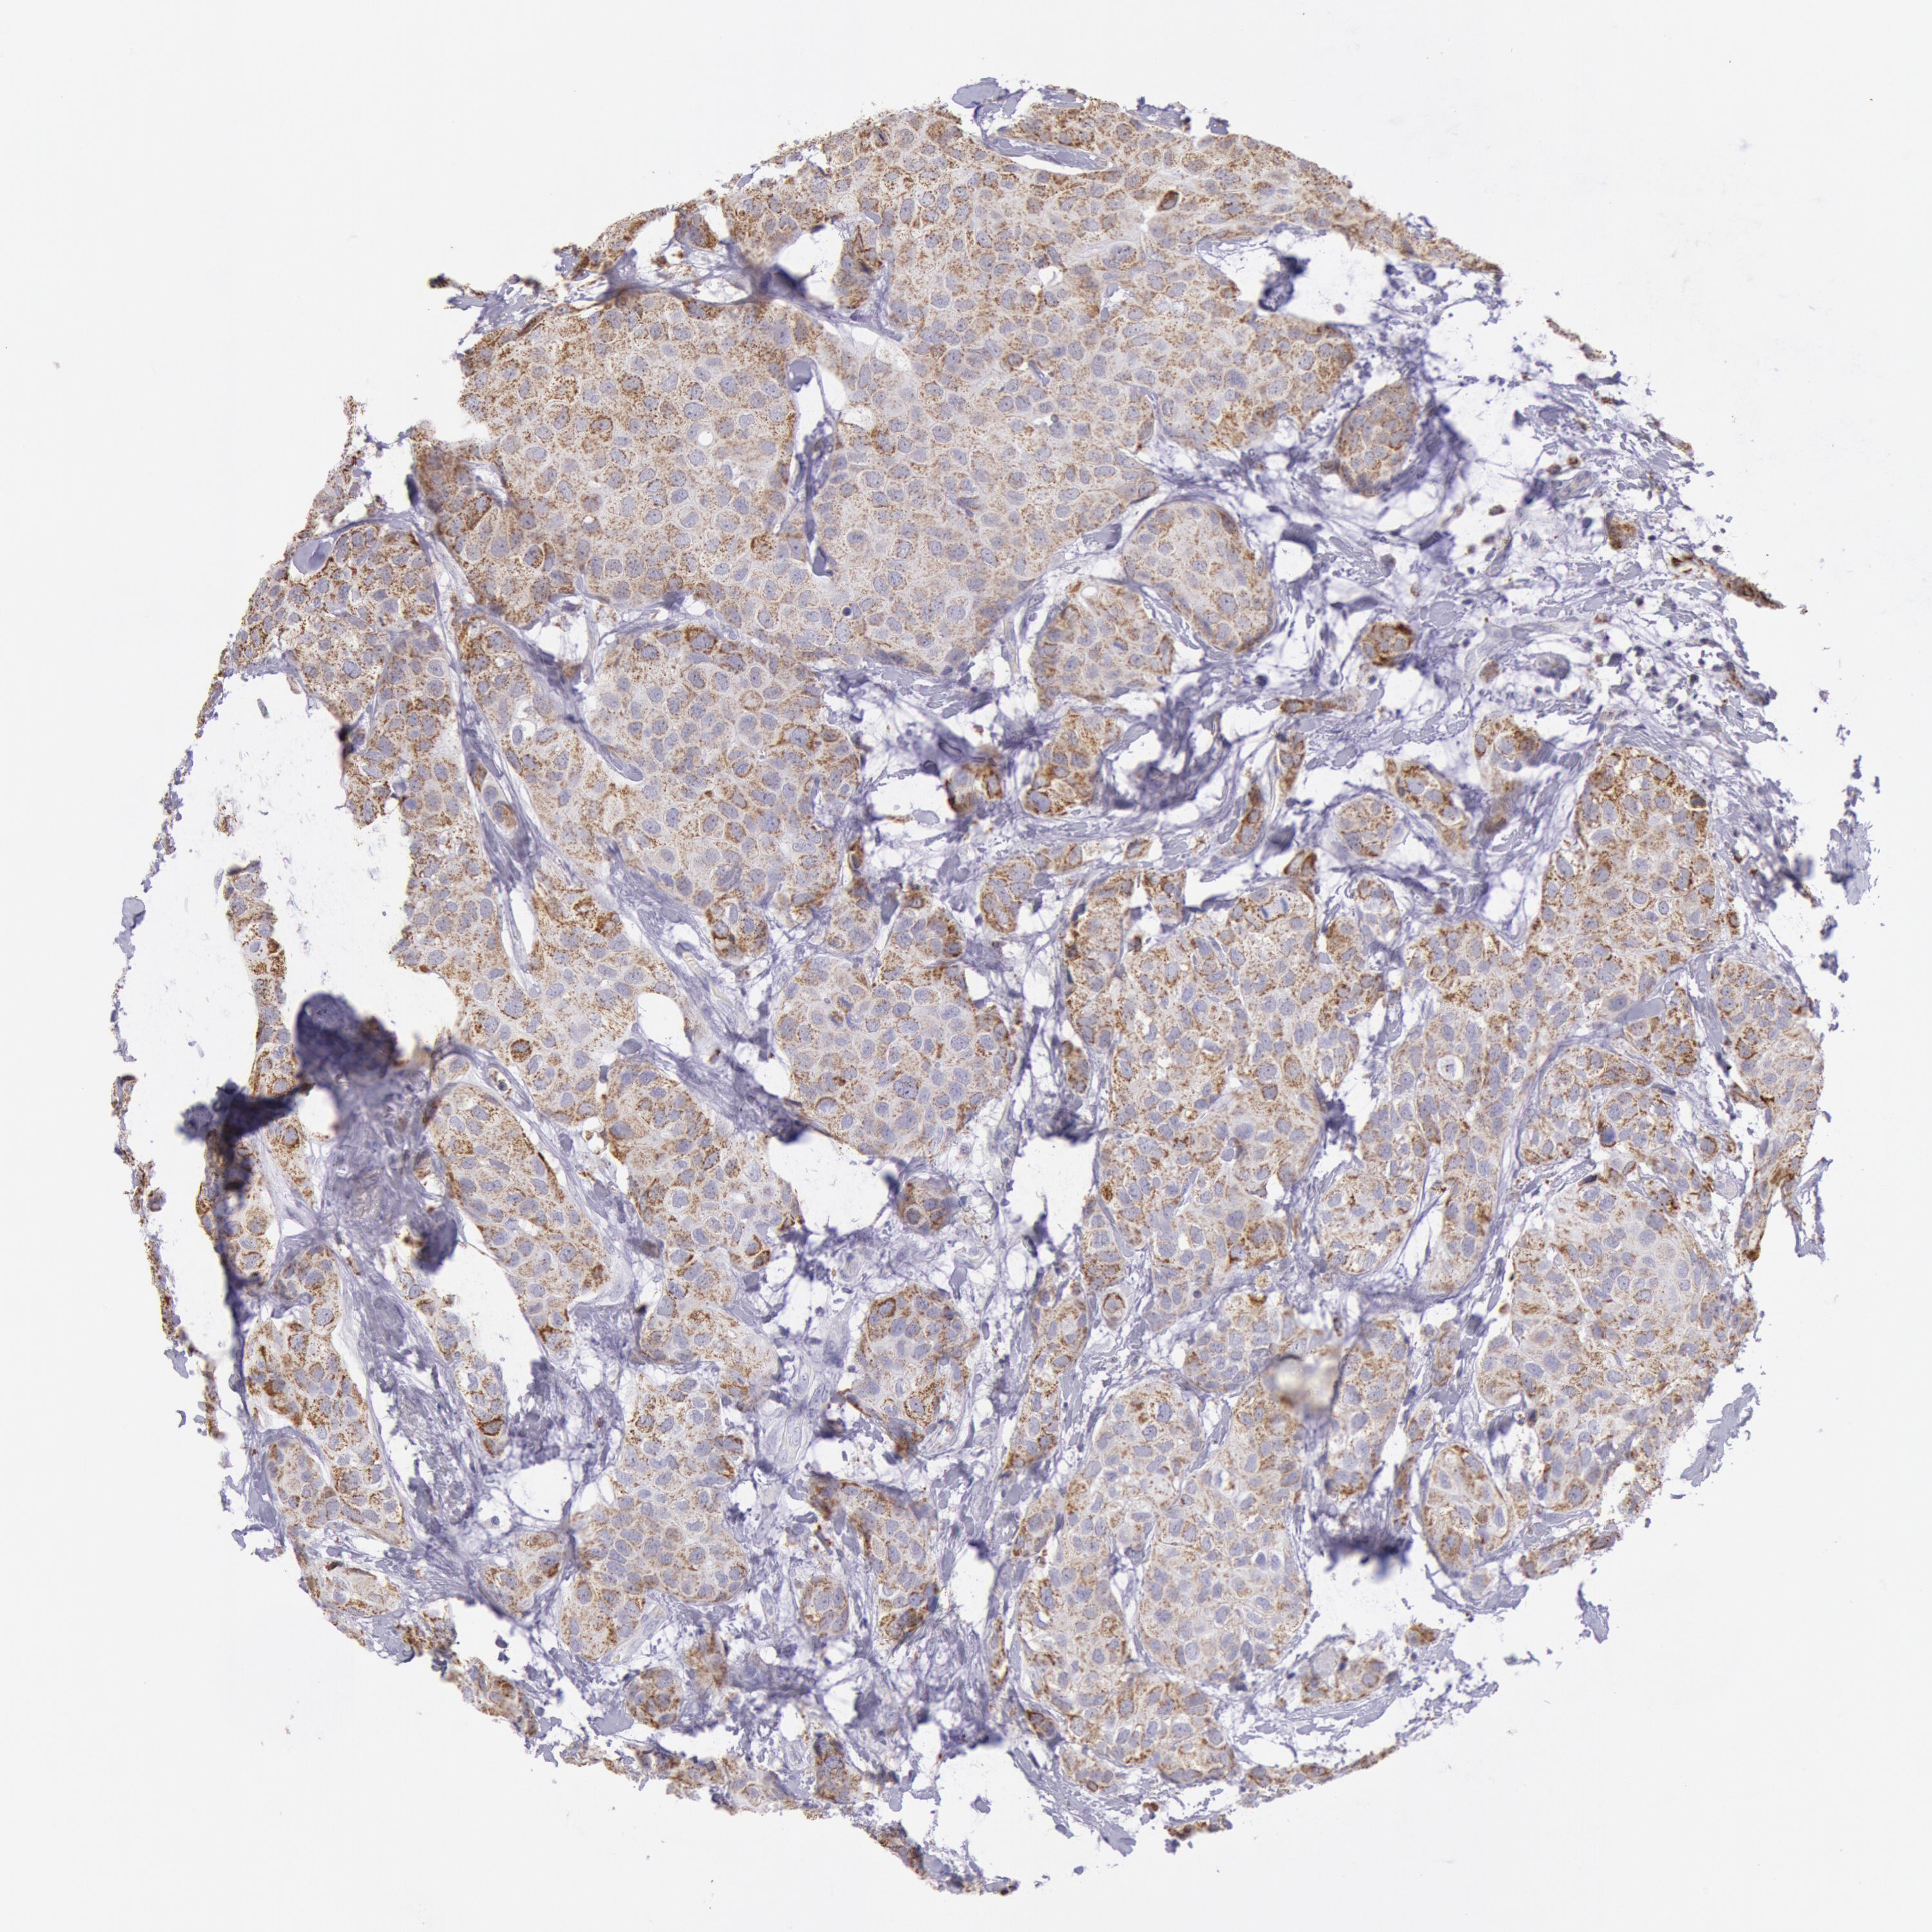

CANCER BREAST CANCER Show tissue menu

BRCA TCGA BRCA VALIDATION PROTEIN EXPRESSION